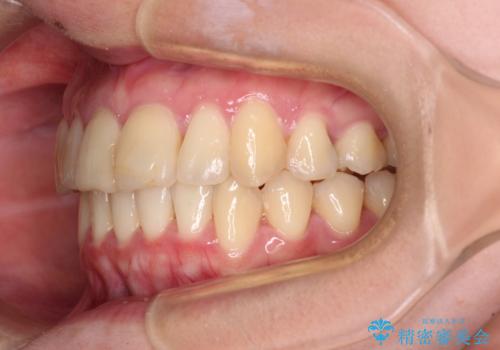

上下前歯のデコボコをきれいに インビザラインによる矯正治療

- 前歯の著しい叢生と前突感を気にして来院された患者様です。

叢生が強いため、事前に前歯をワイヤー矯正で速やかに叢生を解消し、その後はインビザラインにて矯正治療を行うこととしました。

ワイヤー矯正を併用したことで前歯の叢生を速やかに解消することができました。

一方口元の突出感を改善するために時間がかかり、2年超を要しましたが、満足のいく仕上がりとなりました。